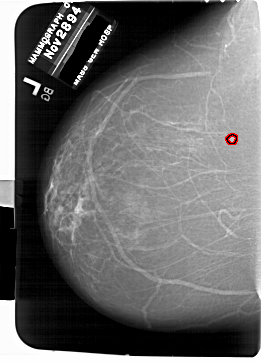

FILE: A_1769_1.LEFT_CC.OVERLAY

TOTAL_ABNORMALITIES 1

ABNORMALITY 1

LESION_TYPE MASS SHAPE LOBULATED MARGINS ILL_DEFINED

ASSESSMENT 4

SUBTLETY 4

PATHOLOGY BENIGN

TOTAL_OUTLINES 1

BOUNDARY